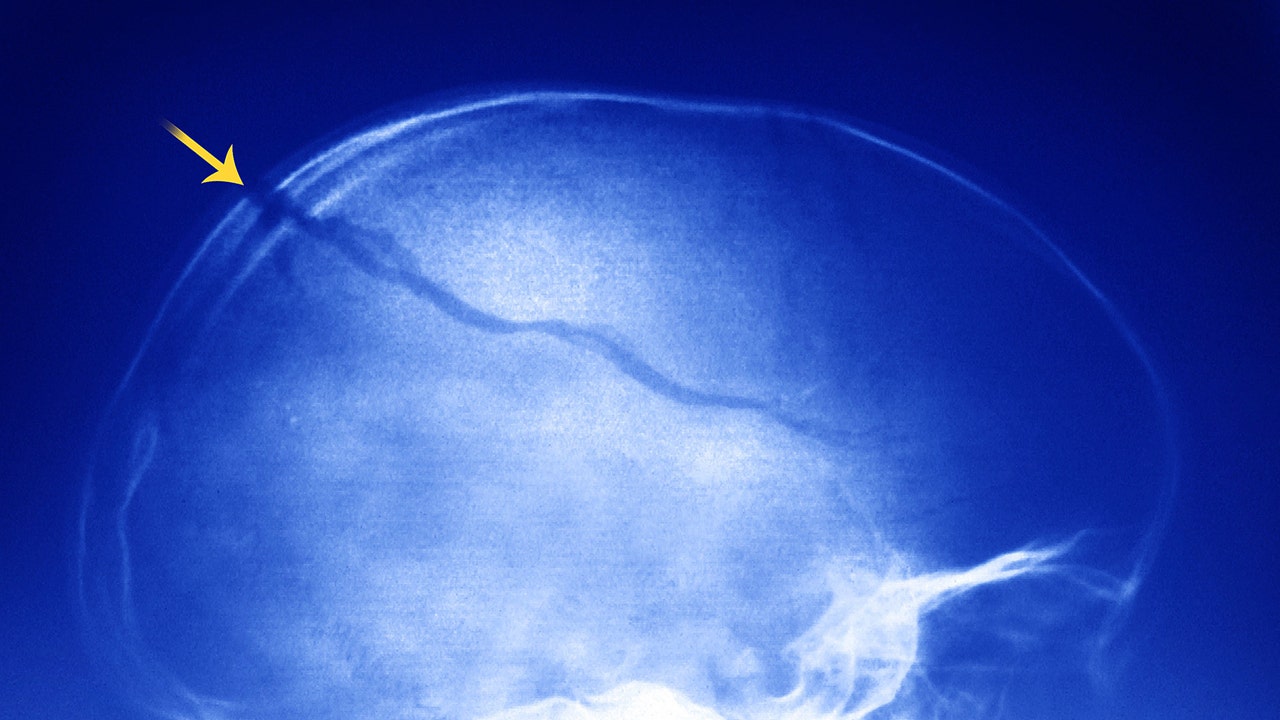

“It can be associated with a variety of serious and even life-threatening injuries including, but not limited to, bruising, hematoma, skull fracture, neck strain, neck fracture, concussion and long-term complications of concussion, bleeding in or around the brain, loss of consciousness, paralysis and death," he said.